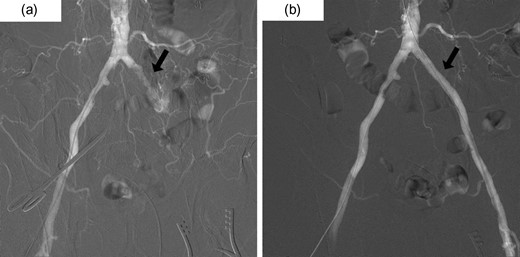

He underwent an elective laparoscopic abdominoperineal resection with a lithotomy position. There was no vascular injury or compression with laparoscopic forceps as far as we were able to recognize retrospectively based on the laparoscopic video and the memory. The duration of surgery was 4 hours and 48 minutes. Blood loss was estimated 100 ml, the urine volume was only 50 ml during the operation. In-out balance during operation divided body weight and time of operation was 6.38 ml/kg/h. The patient reported a severe pain in the left leg, when he woke up post-operatively. The left leg was pale and cold, associating sensory abnormality and motor dysfunction; left pedal and popliteal pulses were absent. A CT scan revealed the contrast interruption of left common iliac artery (CIA) over 11.5 cm and suspected to be due to an arterial thrombosis (Fig. 2). Under the local anesthetic technique, the left femoral artery was exposed and performed thrombectomy with a 5Fr Fogarty catheter. After a new clot was removed, aortography revealed persistent stenosis in left iliac artery. Consequently, a Percutaneous transluminal angioplasty (PTA) with stent (Express LD 8 × 37 mm) was added (Fig. 3) via left femoral artery. Blood perfusion in his left leg improved markedly immediately post PTA. The patient was transferred to the intensive care unit for two days due to the complications with a rhabdomyolysis (creatinine phosphokinase up to 23 598 IU/l). The patient started walking 5 days post-surgery, however, the patient was left with the numbness in his left lower leg. A heparinization had been commenced on the postoperative day 1, then this was switched to the cilostazol prior to the discharge for home. We note that the patient continued reporting the left lower leg numbness even one year past the surgery.

Postoperative 3D-contrast enhanced CT revealed the complete obstruction of left common iliac artery (CIA). The sagittal section through the left iliac artery and the graph of left CIA’s internal diameter showed significant stenosis.